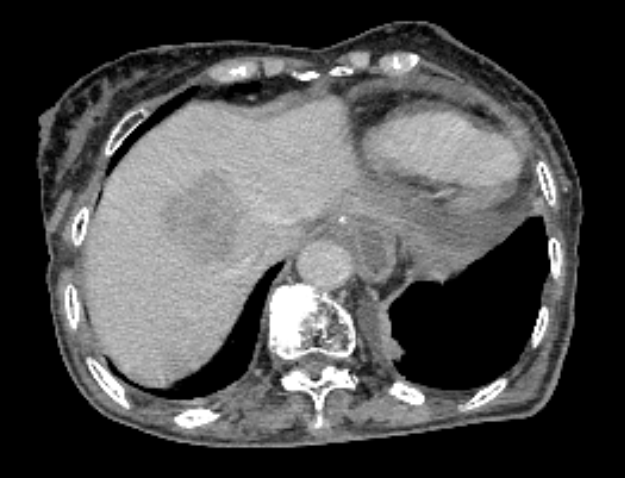

患者术前CT:

1、术前精准规划:制定三维治疗计划系统(TPS)勾画肿瘤靶区,精确规划粒子的分布范围、数量、活度及间距,确保粒子均匀覆盖整个病灶,同时避开周围的血管、胆管等正常组织,实现“局部剂量高、周围正常组织损伤小”的治疗目标。